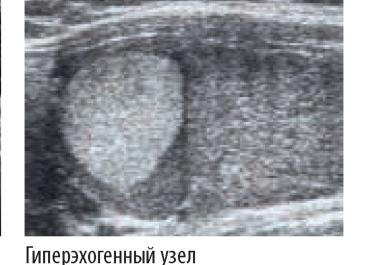

- Повышенная (гиперэхогенность) – отклонение от нормы, связанное с разрастанием соединительной ткани или отложением солей кальция. Это более светлые участки, чем другие.